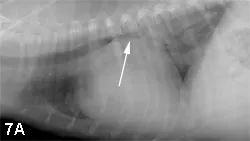

Within the middle mediastinum, the most obvious structure is the cardiac silhouette. Initially, microcardia and cardiomegaly should be noted. In a dog, specific right- or left-side cardiomegaly or cardiac chamber enlargement can be documented; this does not hold true in the cat. Typically, neither the esophagus nor tracheobronchial lymph nodes are visualized in thoracic radiographs from the small animal patient. Enlargement of the tracheobronchial lymph nodes will result in deviation of the right and left cranial bronchi laterally away from the principle bronchial bifurcation, also known as the carina. The carina will be displaced ventrally by enlargement of the central tracheobronchial lymph node, whereas left atrial enlargement will result in dorsal elevation of the carina (Figure 7).

Right lateral radiograph from a dog with left atrial enlargement (A). Note the dorsal deviation of the carina secondary to severe left atrial enlargement (arrow). In a radiograph obtained from a dog with enlargement of the central tracheobronchial lymph node (B), ventral deviation of the carina can be seen (arrow).